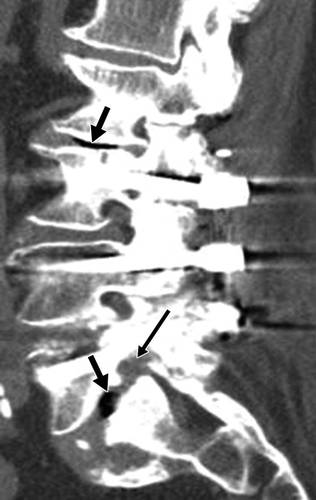

图5A-67岁男子L3-L5腰椎融合3年后复发性左侧放射性疼痛。MDCT图像显示左侧椎弓根螺钉(L3-L5)。 左L5-S1神经孔被表示盘或瘢痕组织的软组织阻塞,L5神经根被压缩(薄箭头)。 L2-L3和L5-S1中的真空现象(粗箭头),表示髓核变性。

图5B-67岁男子L3-L5腰椎融合3年后复发性左侧放射性疼痛。矢状MDCT图像显示标记的椎间盘突出(薄箭头)和L5椎体向前滑脱;手术后肥厚的增生组织导致L5-S1(长厚箭头)椎管狭窄;在L1-2和L2-3处可见后椎体后缘骨质疏松和椎间盘膨突(短粗箭头)。